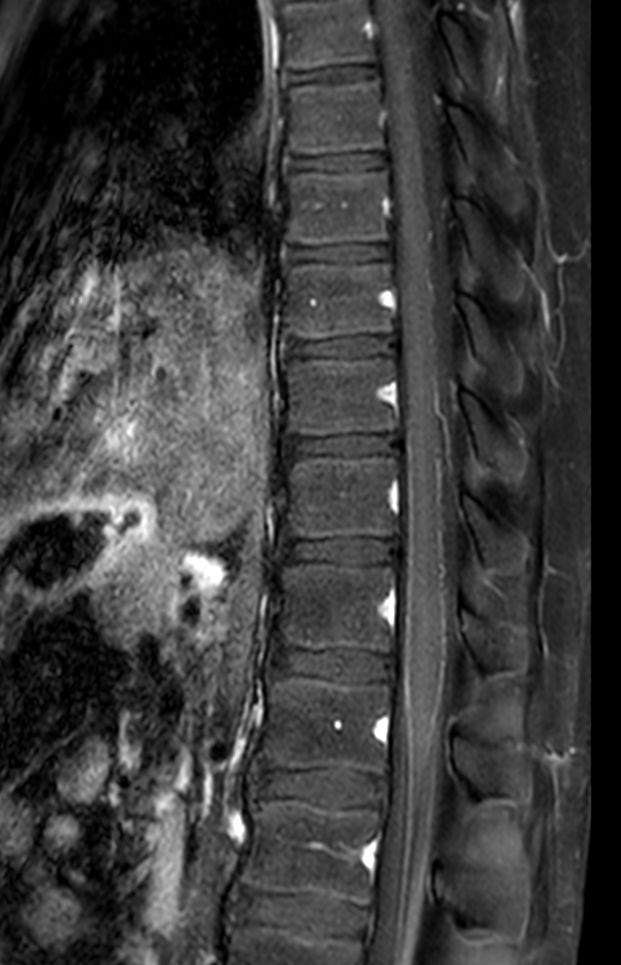

Sagittal T2w TSE (T-Spine)